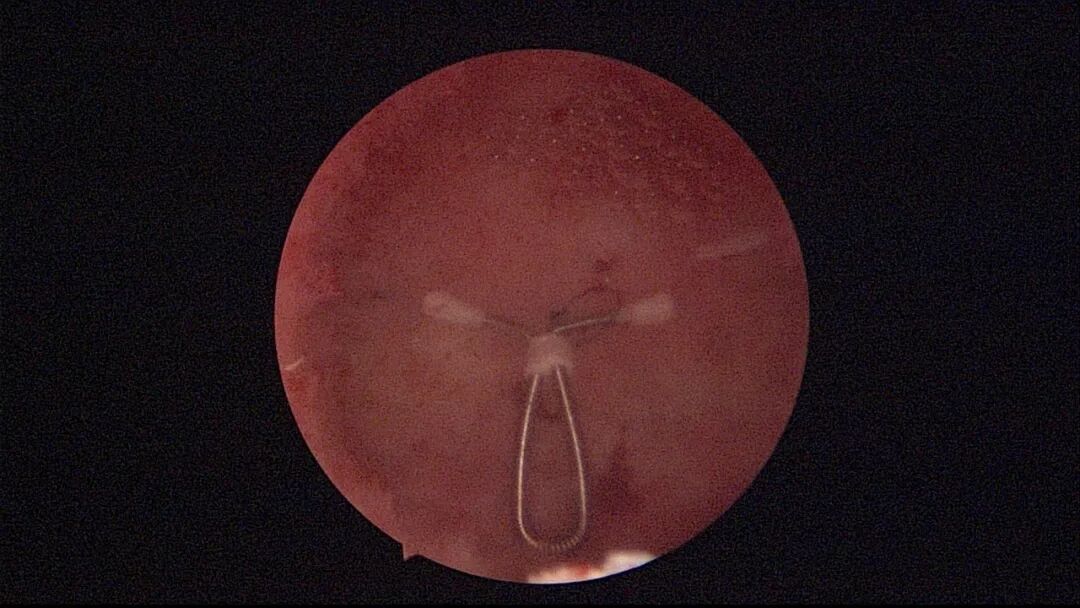

自制线结扣宫腔镜下锚定节育环,可以用不可吸收线做结,也可以用节育环尾丝做结,线结做成小球形或短棒形,拉紧拉实,直径约1mm。线圈绕数次拉紧线结呈逗点状,线圈绕10次以上拉紧线结呈小棒状,三重外科结拉紧线结近似球形,选择三重外科结为好,每个手术医生可能会有不同的打结方法。微型剪刀插入宫底肌层约0.5cm向不同方向撑开,形成口小底大的线结扣固定隧道,用异物钳将线结扣推入隧道内,隧道周围组织可用电针电凝收缩加强固定。弊端是做一个完美的线结扣比较困难,将线结扣推入隧道也比较困难,力度大小难以精准掌握和控制,是否固定牢固不好评估,可作为备用方案掌握。

自制线结扣示意图说明